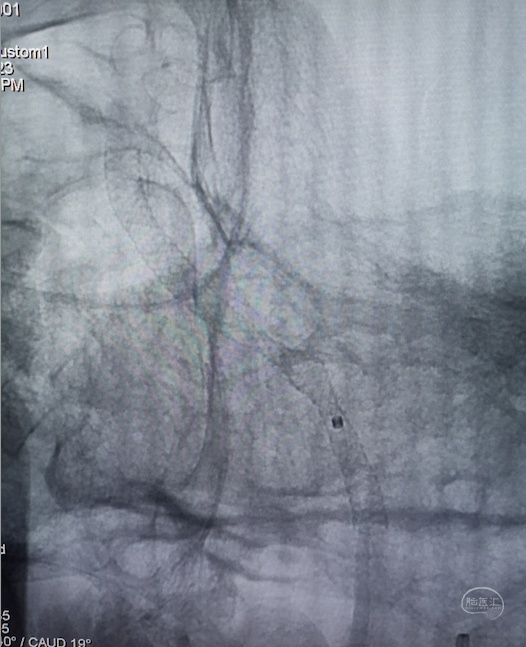

股动脉入路,置入8F长鞘,6F 115cm Navien™ 颅内支撑导管超选至左侧椎动脉V4段。

将Phenom™ 27微导管超选进入左侧大脑后动脉内,释放一枚3.25×35mm Pipeline™ Flex血流导向密网支架,远端定位在动脉瘤以远7mm,在动脉瘤处推密,近端定位在PICA起始部上端或远端,支架打开顺利。导引导管内推注替罗非班12mL,支架导管及微导管常规按摩,促进支架贴壁。

支架CT: